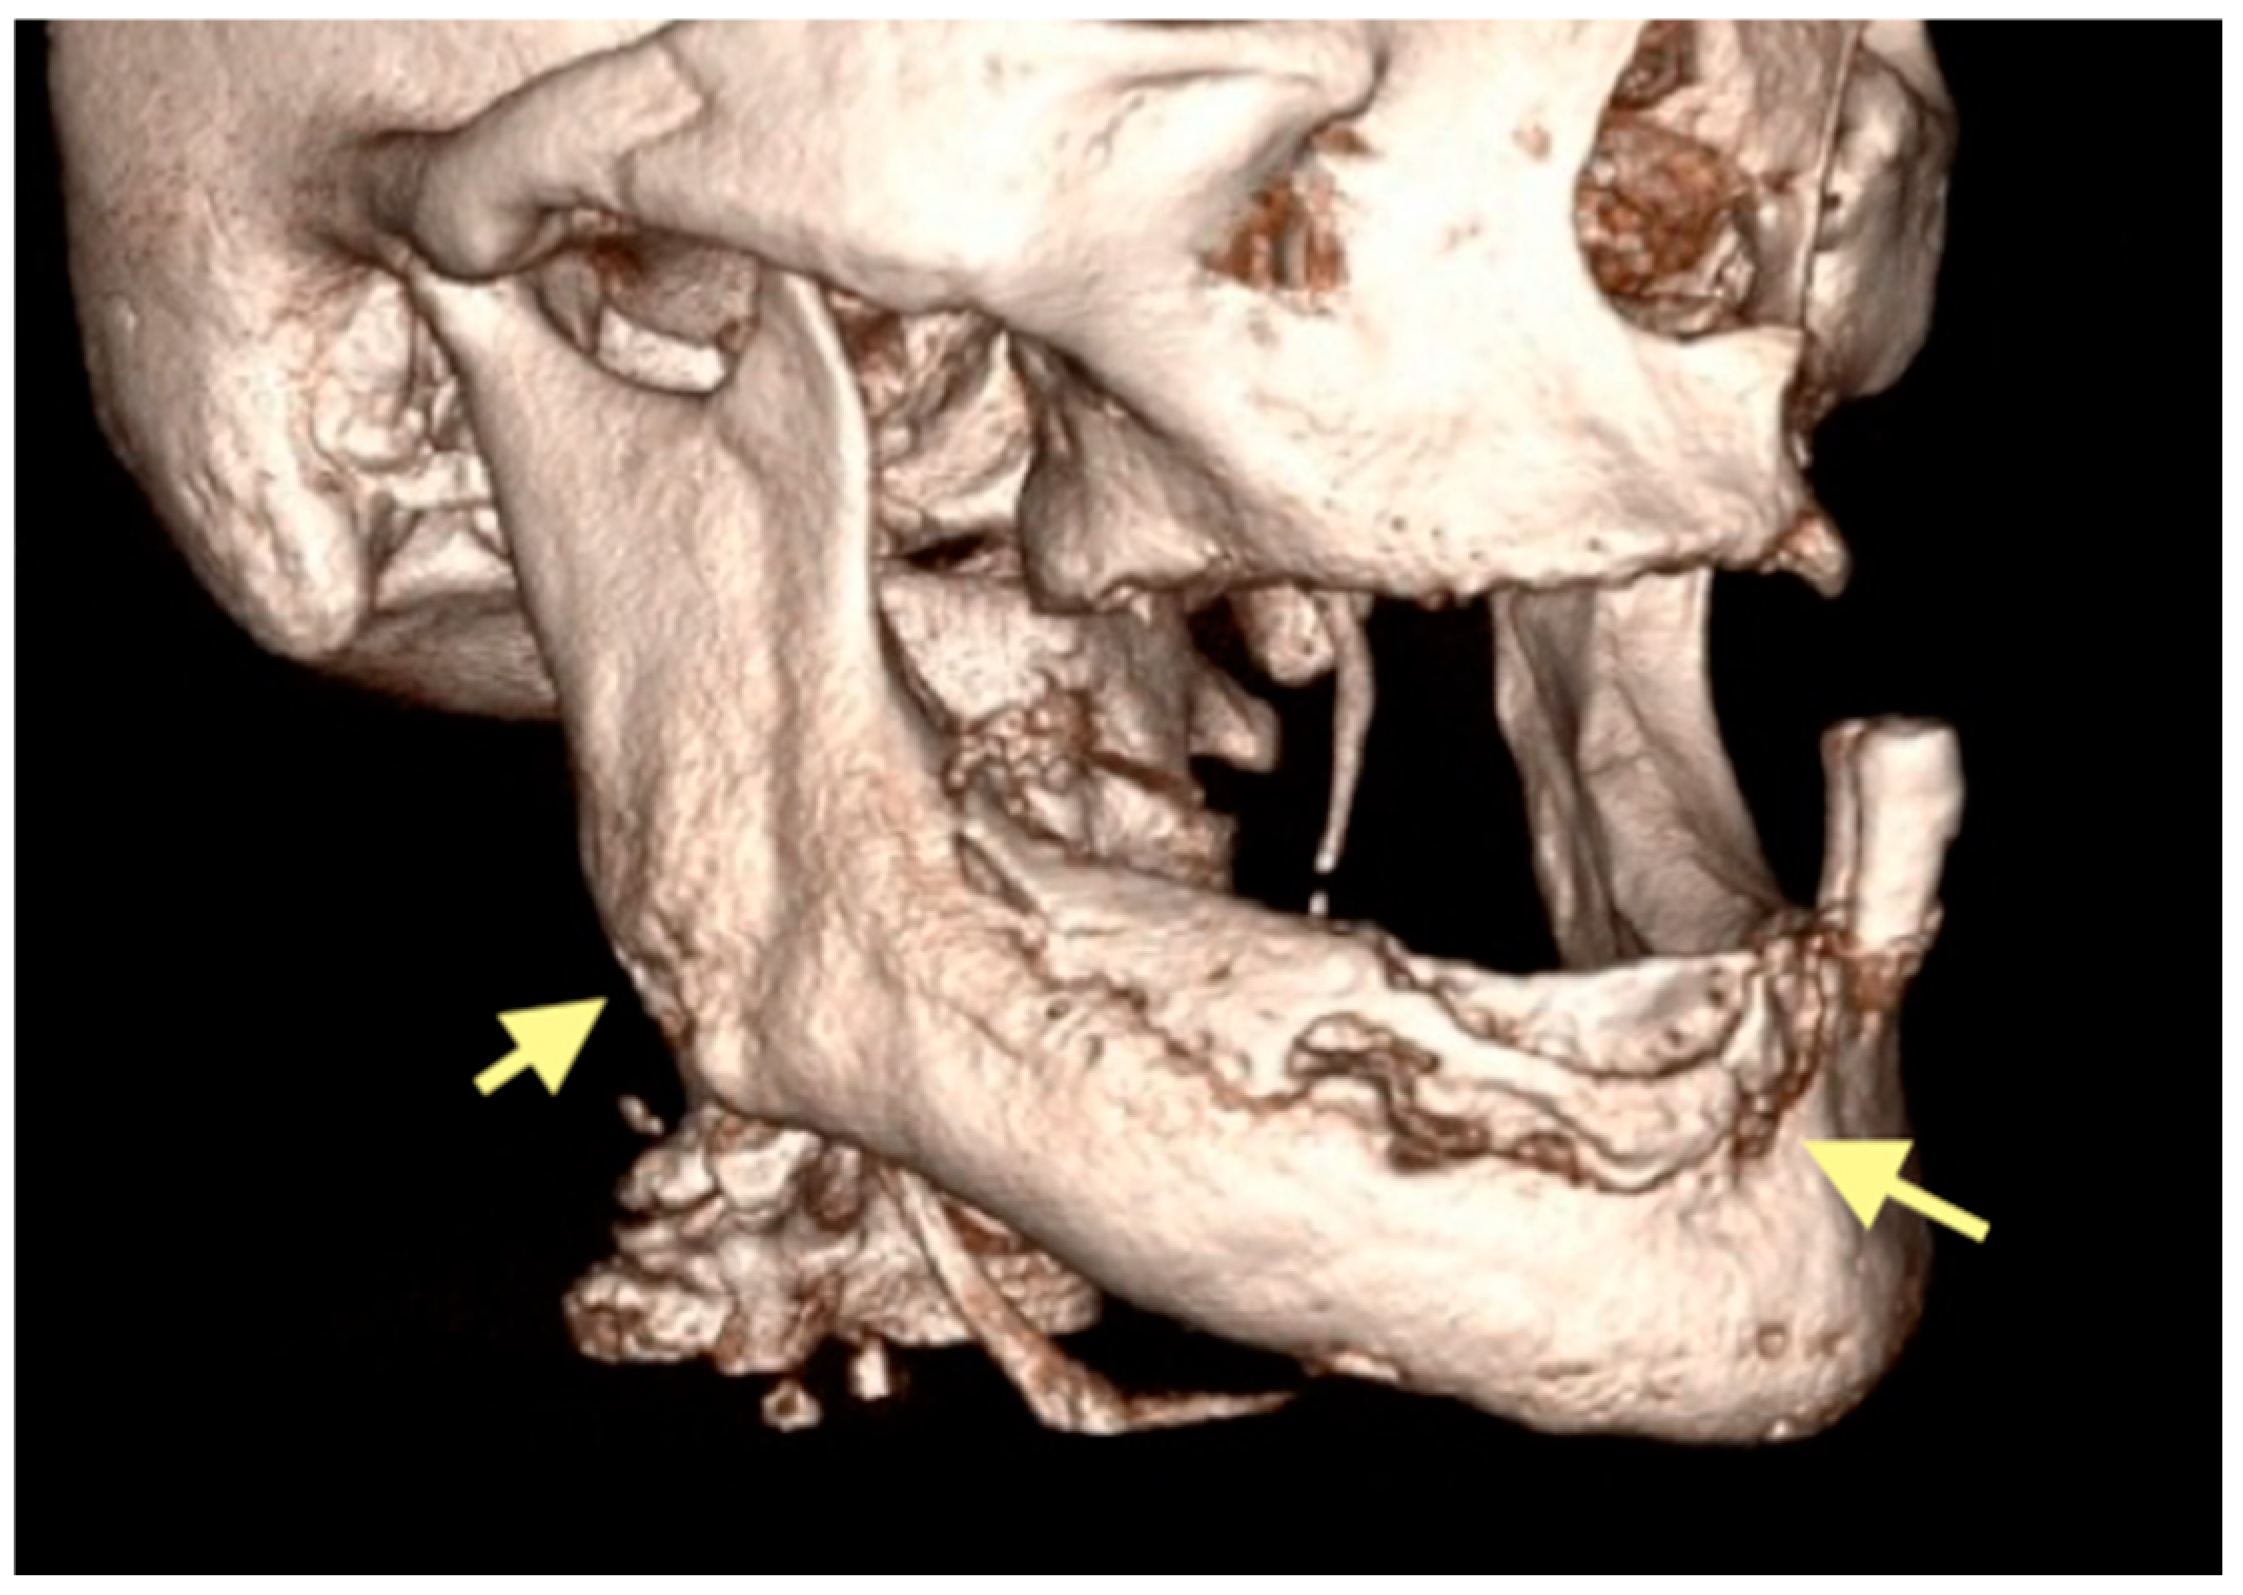

2.3. The Third Case (See Table 1)

The third patient was a 75-year-old female with osteonecrosis of the mandible and maxilla in the fourth and in the second quadrant (see Figure 7, Figure 8 and Figure 9). The patient had third-stage jaw osteonecrosis. In 2023, the patient was diagnosed with osteonecrosis of the upper and lower jaw caused by antiresorptive therapy (until August 2021, the patient regularly used Zolendronic acid; then, this drug was replaced by the RANKL inhibitor Denosumab). The treatment was periodically complicated by submandibular and submental abscesses. In addition, due to the progression of the underlying disease, constant courses in chemotherapy were administered. The patient underwent three operations, which included sequestrectomy of the jaw with simultaneous use of A-PRF, antrotomy with revision of the maxillary sinus, closure of the oroantral communication, and opening and revision of abscesses of the soft tissues (see Figure 10 and Figure 11)

Figure 7.

CT of the head and facial bones (16 December 2024).